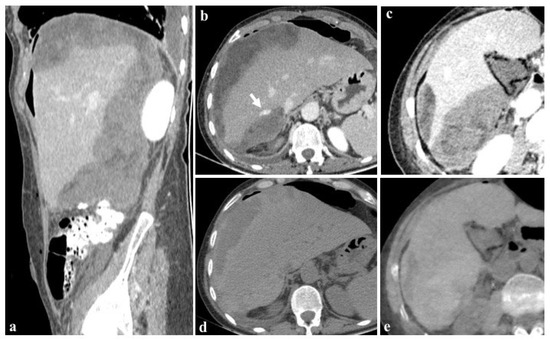

The utilization of iterative reconstruction algorithms is another significant factor contributing to dose reduction [66]. These algorithms facilitate the reduction in CT image noise while preserving the spatial resolution and contrast-to-noise ratio (CNR) [67]. Furthermore, the integration of virtual non-contrast (VNC) images, as in the case shown in Figure 7, obviates the necessity for true non-contrast (TNC) acquisitions, resulting in a substantial reduction in radiation dose exposure ranging from 32.9% [60] to 57% [68,69,70,71,72].

Figure 7.

Images at 40 keV after 80 mL contrast medium (a–c) show the presence of an active bleeding liver ((b), arrow) and a diffuse subcapsular hematoma after cholecystectomy in a 76-year-old woman. The patient was rapidly referred to percutaneous angiographic treatment. True non-contrast imaging (d) may be replaced by virtual non-contrast reconstructions (e) in the evaluation of subcapsular hematoma avoiding unnecessary scans without contrast medium during post-embolization follow-up.